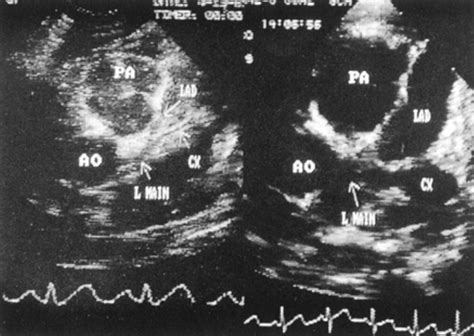

The most significant concern regarding Kawasaki Disease in adults is the impact on the coronary arteries. Inflammation can lead to the weakening of the arterial walls, resulting in aneurysms—bulges in the vessel wall. These aneurysms can lead to blood clots, heart attacks, or even sudden death. Because the heart undergoes physiological changes during the transition to adulthood, the management of these aneurysms often requires a specialized multidisciplinary team, including rheumatologists, cardiologists, and infectious disease specialists.

For those who have been diagnosed with Kawasaki Disease in adults, the management does not end when the fever disappears. Long-term follow-up is essential. Patients who developed coronary artery aneurysms must undergo regular cardiac imaging, such as echocardiograms, cardiac MRIs, or CT angiograms. Depending on the severity of the damage, some patients may require lifelong anti-platelet therapy or other cardiac medications to manage blood pressure and cholesterol levels.